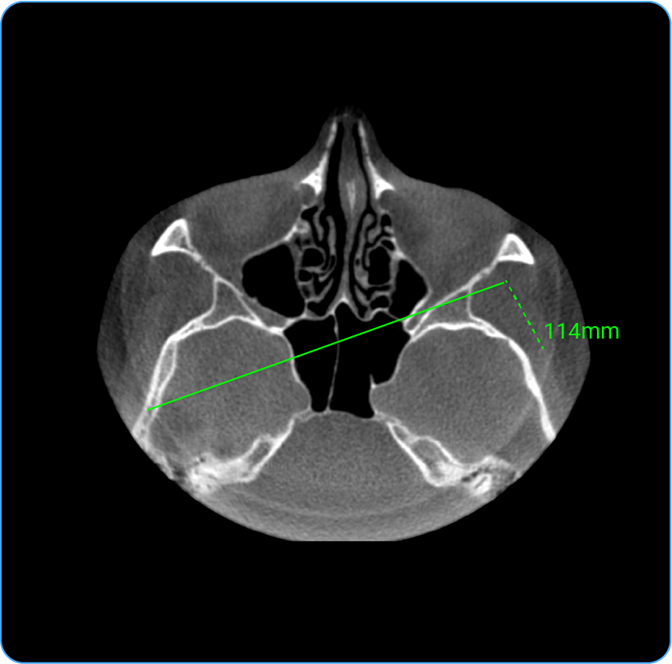

How Do I Measure Length?

- Usage: Measure distance between two points.

- Hotkey: Press D.

- Clinical Utility: Helps measure anatomical structures or lesion sizes.

- Locate the Length tool on the wheel and click on it to calculate the distance between two points on the image, useful for measuring anatomical structures.

- Length: Locate the Length tool on the wheel and click on it to calculate the distance between two points on the image, useful for measuring anatomical structures.